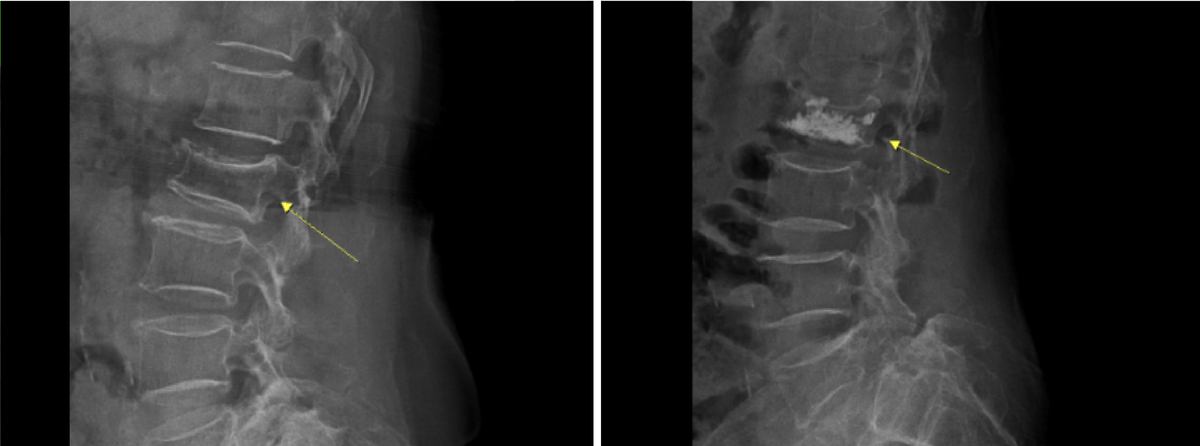

진단은 X-ray를 통해 척추뼈가 눌린 상태를 확인하는 게 기본이다. 다만 골절의 시기나 신경 압박 여부까지 확인하기 위해 MRI나 CT를 추가로 시행하기도 하며, 골다공증 여부를 확인하기 위한 골밀도검사도 중요하다.

하지만 보존적 치료에도 통증이 지속되거나 척추가 더 주저앉는 경우에는 척추체 성형술을 고려할 수 있다. 척추체 성형술은 특수 바늘을 이용해 골절 부위에 골시멘트를 주입해 척추를 안정화시키는 치료로, 비교적 빠른 통증 완화와 일상 복귀가 가능하다는 장점이 있다. 국소마취로 진행되기 때문에 고령 환자에게도 부담이 적은 편이다. 시술은 영상장비를 통해 병변 위치를 확인하면서 진행되며, 골시멘트가 굳으면서 척추체를 지지해 통증을 줄이고 추가적인 변형을 예방한다.